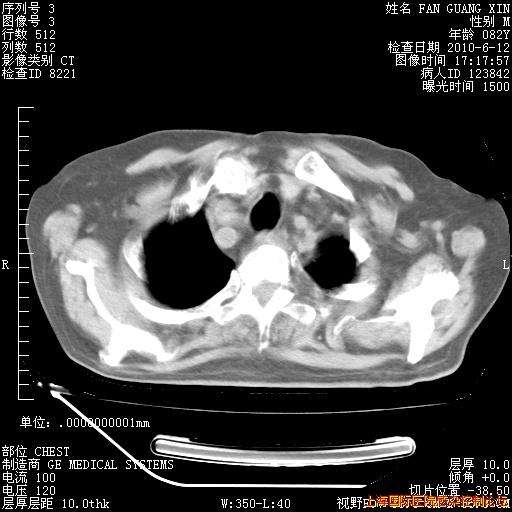

6月12日肺窗

补发6月12日肺部CT肺窗